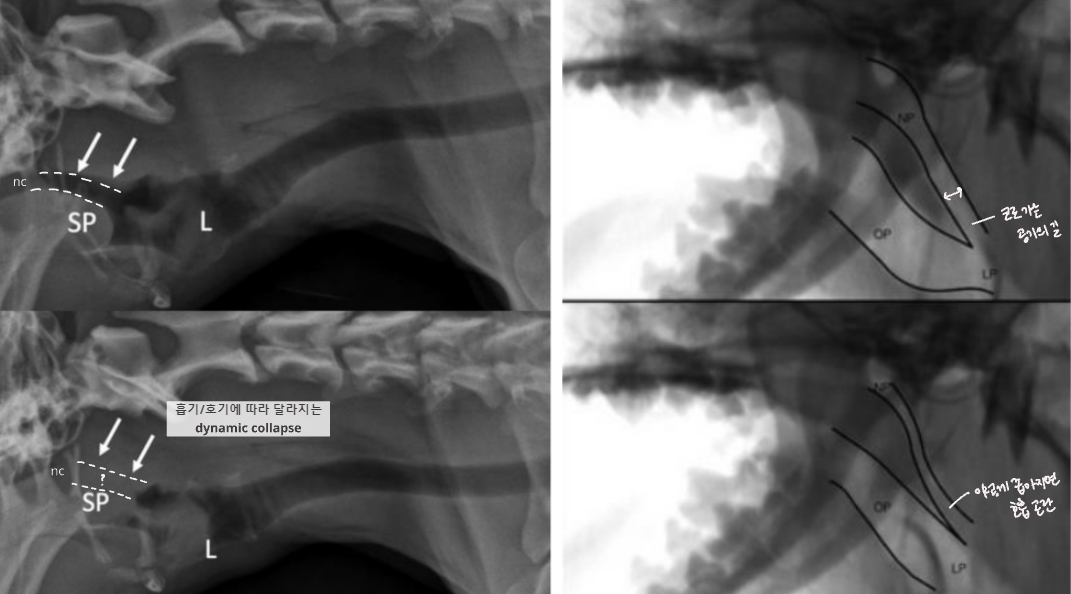

- English bulldog, Pug, Pekingese, French Bulldog, Bonston Terrier.. ์์ธ - Skull์ base๊ฐ ์ ์ ์ ์ผ๋ก ์งง์ - ๊ตฌ์กฐ์ ์ผ๋ก ์ผ๊ตด์ด ์งง์ ๊ตฌ์กฐ๊ฐ ๊ณผ๋ฐ๋จ Complex - stenotic nares (๋น๊ณตํ์ฐฉ) - soft palate edema & elongation (์ฐ๊ตฌ๊ฐ๋ ธ์ฅ) - laryngeal edema, saccules, collapase, paralysis - (dynamic) pharyngeal collapse GI complication - Hiatal hernia - gastroesophageal reflux (์ญ๋ฅ์ฑ ์๋์ผ) |

| Pharyngeal collapse : ํธ๊ธฐ ๋ ์ข์์ง - ์ฆ์์ ํก๊ธฐ์์ ๋ ์ฌํจ (ํก๊ธฐ์ฑ ํธํก๊ณค๋) ![]() ![]() |